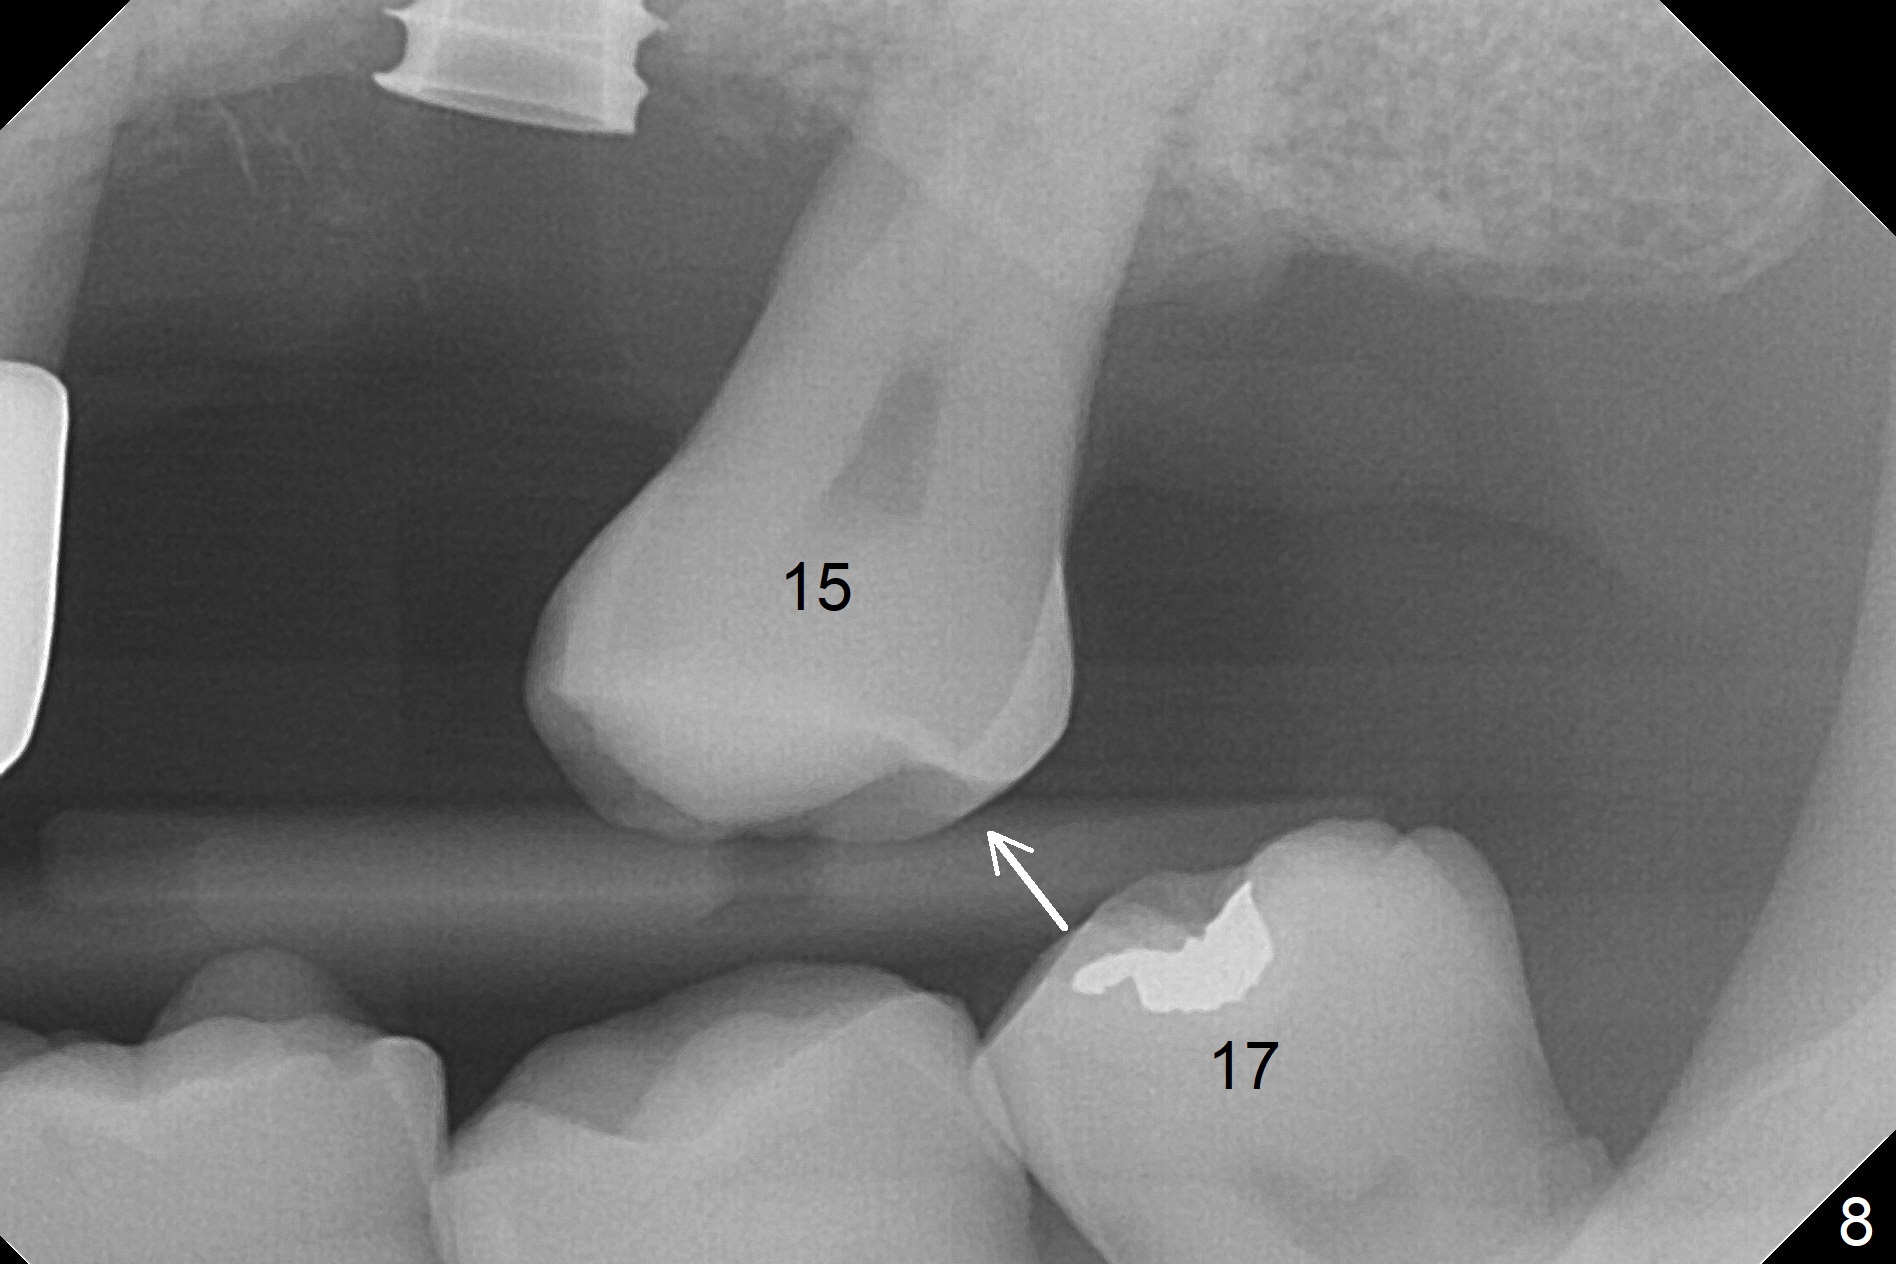

The amount of the bone graft mesial and distal the implant seems to reduce 3 and 4 months postop, respectively (Fig.6,7 arrowheads). When the acrylic is cut off 4 months postop, the bone graft is loose. The gingiva is unhealthy. The abutment and implant are loose. A healing abutment is placed (5x4 mm). The implant is torqued to 35 Ncm 6 months postop with the healing abutment reapplied. The patient will return for follow up nearly 9 months postop. A larger healing abutment will be used if the implant is stable. Two weeks later, use a smaller restorative abutment for easy impression. In fact the implant is unstable with #15 mesial shift due to abnormal occlusion with #17 (Fig.8). Bone density around the implant is low (* in Fig.9 (PA), 10,11 (CT sagittal, coronal sections)). A healing screw is placed for self healing. A 2nd option is to remove the implant (Fig.12), BEB (Fig.13) and place the implant deeper (Fig.14) or larger one (5.5-6.5x13 mm). The 3rd option is to place larger and longer implants (Fig.15 (tapered), 16 (cylindrical)). The implant access has partially closed 14 months postop, but there is a small buccal opening with sanguine exudate. Incision reveals severe bone loss around the implant; the mobile tooth #15 is extracted (Fig.17). After debridement and irrigation with normal saline, Vera Graft (Fig.18 *) and Collagen plug are placed with periodontal dressing.